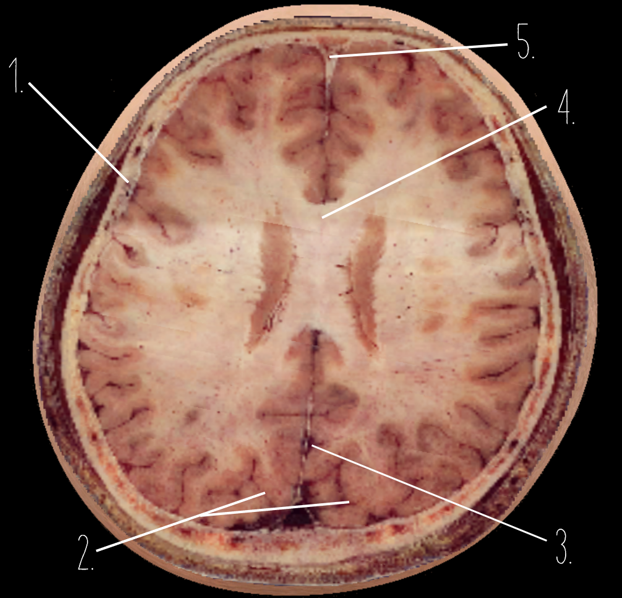

1?

Temporal Bone

2?

Occipital Lobe

3?

Straight Sinus

4?

Body of corpus callosum

5?

Superior Sagittal Sinus